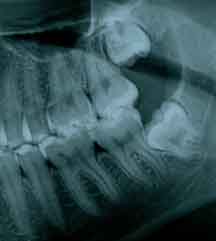

ASPECTO DE SISO INCLUSO:

É possível que em alguns casos os dentes do siso nem cheguem a nascer, ficando inclusos ou aparecendo só uma parte na boca, chamado de semi-inclusos e, também podendo ficar travado nos dentes vizinhos, quando dizemos que ele está impactado.

Os dentes inclusos são aqueles que se encontram dentro do osso ou com parte dentro do osso e parte dentro da gengiva, sem terem nascidos, embora já tenha passado a época normal para a sua erupção. Isto acontece, na maioria das vezes, por falta de espaço na arcada dentária ou pelo fato do dente vizinho estar desalinhado, impedindo assim seu nascimento, ou, ainda, por resistência do tecido ósseo.

Para saber se a pessoa vai ter ou não os dentes do siso e se eles vão causar algum problema, é necessário um exame radiográfico.

A radiografia panorâmica ou tomografia são os mais utilizados. Além de mostrar a presença ou não dos mesmos, mostram sua relação com os órgãos vizinhos, tais como dentes, nervo alveolar inferior e cavidade sinusal.